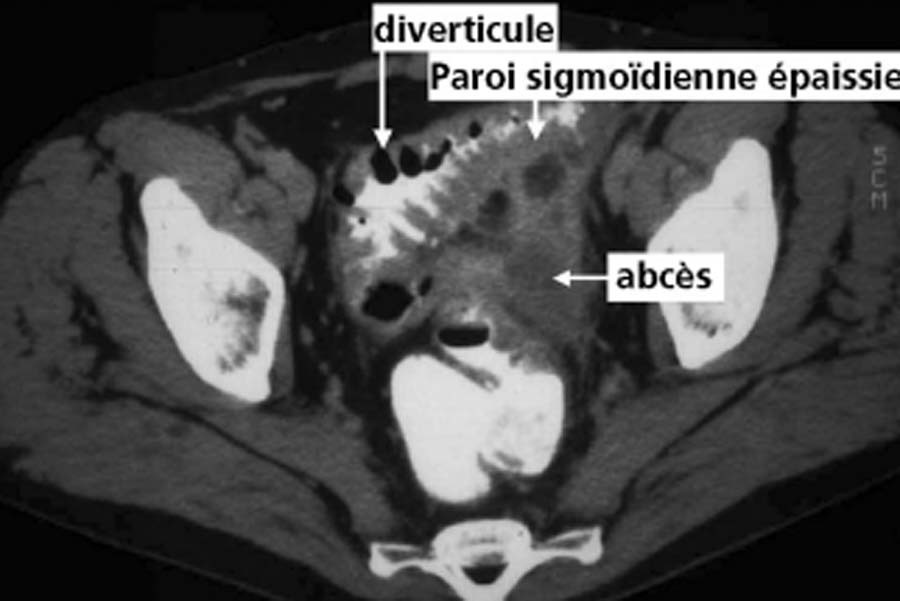

24

Q

Le patient a une diverticulite. Devant persitance fièvre et augmentation du sd inflammatoire à 48h on réalise le TDM suivant. Vu la taille de l’abcès (>5 cm on va dire), quelle CAT?

A

drainage de l’abcès: ponction percutanée écho ou scanno-guidée; OU drainage chirurgical si percut impossible (avec RDC à distance)